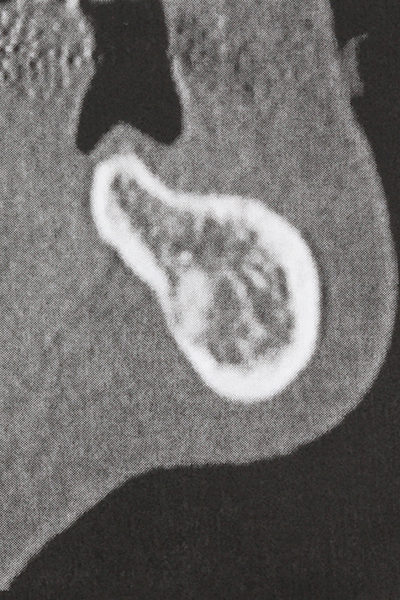

Пиезохирургията има допълнителни предимства при събиране на костни блокове. В допълнение към високата прецизност при остеотомията, описана по-горе, употребата на фините режещи накрайници значително намаляват загубата на материал. Голяма загуба на материал по време на събиране може да се очаква с дебелите накрайници, особено при употреба на борери Линдеман (Lakshmiganthan, Gokulanathan et al. 2012). Базалното разделяне, което е необходимо, особено за присадка на блок при ретромолар, е улеснено от специално създадени правоъгълни триони. В резултат на това, пиезохирургията е разглеждана като прецизна, улеснена и безопасна процедура за събиране на костни блокове в ретромоларното пространство (Happe 2007) (Фиг. 1-12).